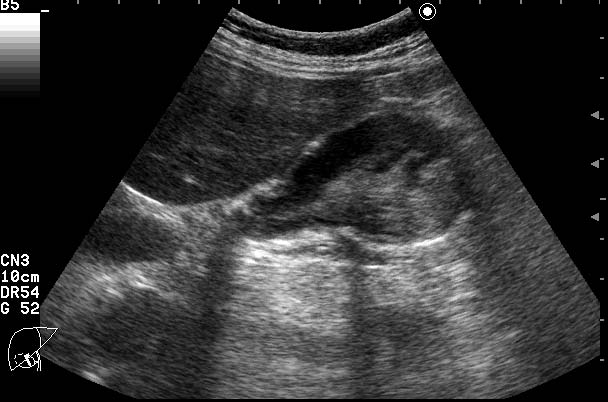

ЖКБ. Эмпиема желчного пузыря.

Женщина 70 лет с болями в правом подреберье и интоксикацией.

Острый калькулезный холецистит,осложненный эмпиемой. Второй вариант-"замазкообразная"желчь в просвете воспаленного пузыря.

Первый вариант мне нравится больше.

Второй маловероятен в связи с описанной клиникой.

О.обструктивный калькулезный холецистит. Эмпиема желчного пузыря.

Но,и первый вариант возможен,стенка дна ж.пузыря НЕЦЕЛАЯ,возможна перфорация.